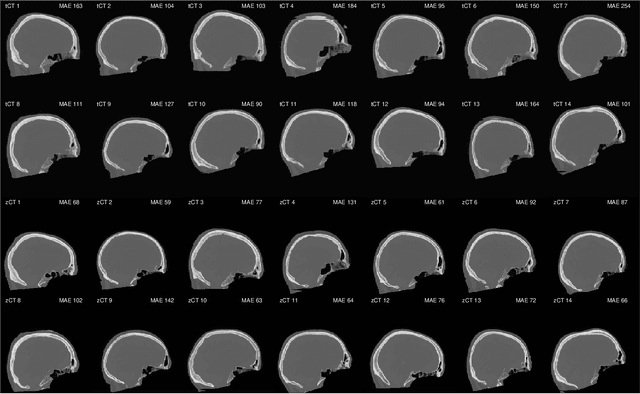

Abstract:Model-based treatment planning for transcranial ultrasound therapy typically involves mapping the acoustic properties of the skull from an x-ray computed tomography (CT) image of the head. Here, three methods for generating pseudo-CT images from magnetic resonance (MR) images were compared as an alternative to CT. A convolutional neural network (U-Net) was trained on paired MR-CT images to generate pseudo-CT images from either T1-weighted or zero-echo time (ZTE) MR images (denoted tCT and zCT, respectively). A direct mapping from ZTE to pseudo-CT was also implemented (denoted cCT). When comparing the pseudo-CT and ground truth CT images for the test set, the mean absolute error was 133, 83, and 145 Hounsfield units (HU) across the whole head, and 398, 222, and 336 HU within the skull for the tCT, zCT, and cCT images, respectively. Ultrasound simulations were also performed using the generated pseudo-CT images and compared to simulations based on CT. An annular array transducer was used targeting the visual or motor cortex. The mean differences in the simulated focal pressure, focal position, and focal volume were 9.9%, 1.5 mm, and 15.1% for simulations based on the tCT images, 5.7%, 0.6 mm, and 5.7% for the zCT, and 6.7%, 0.9 mm, and 12.1% for the cCT. The improved results for images mapped from ZTE highlight the advantage of using imaging sequences which improve contrast of the skull bone. Overall, these results demonstrate that acoustic simulations based on MR images can give comparable accuracy to those based on CT.